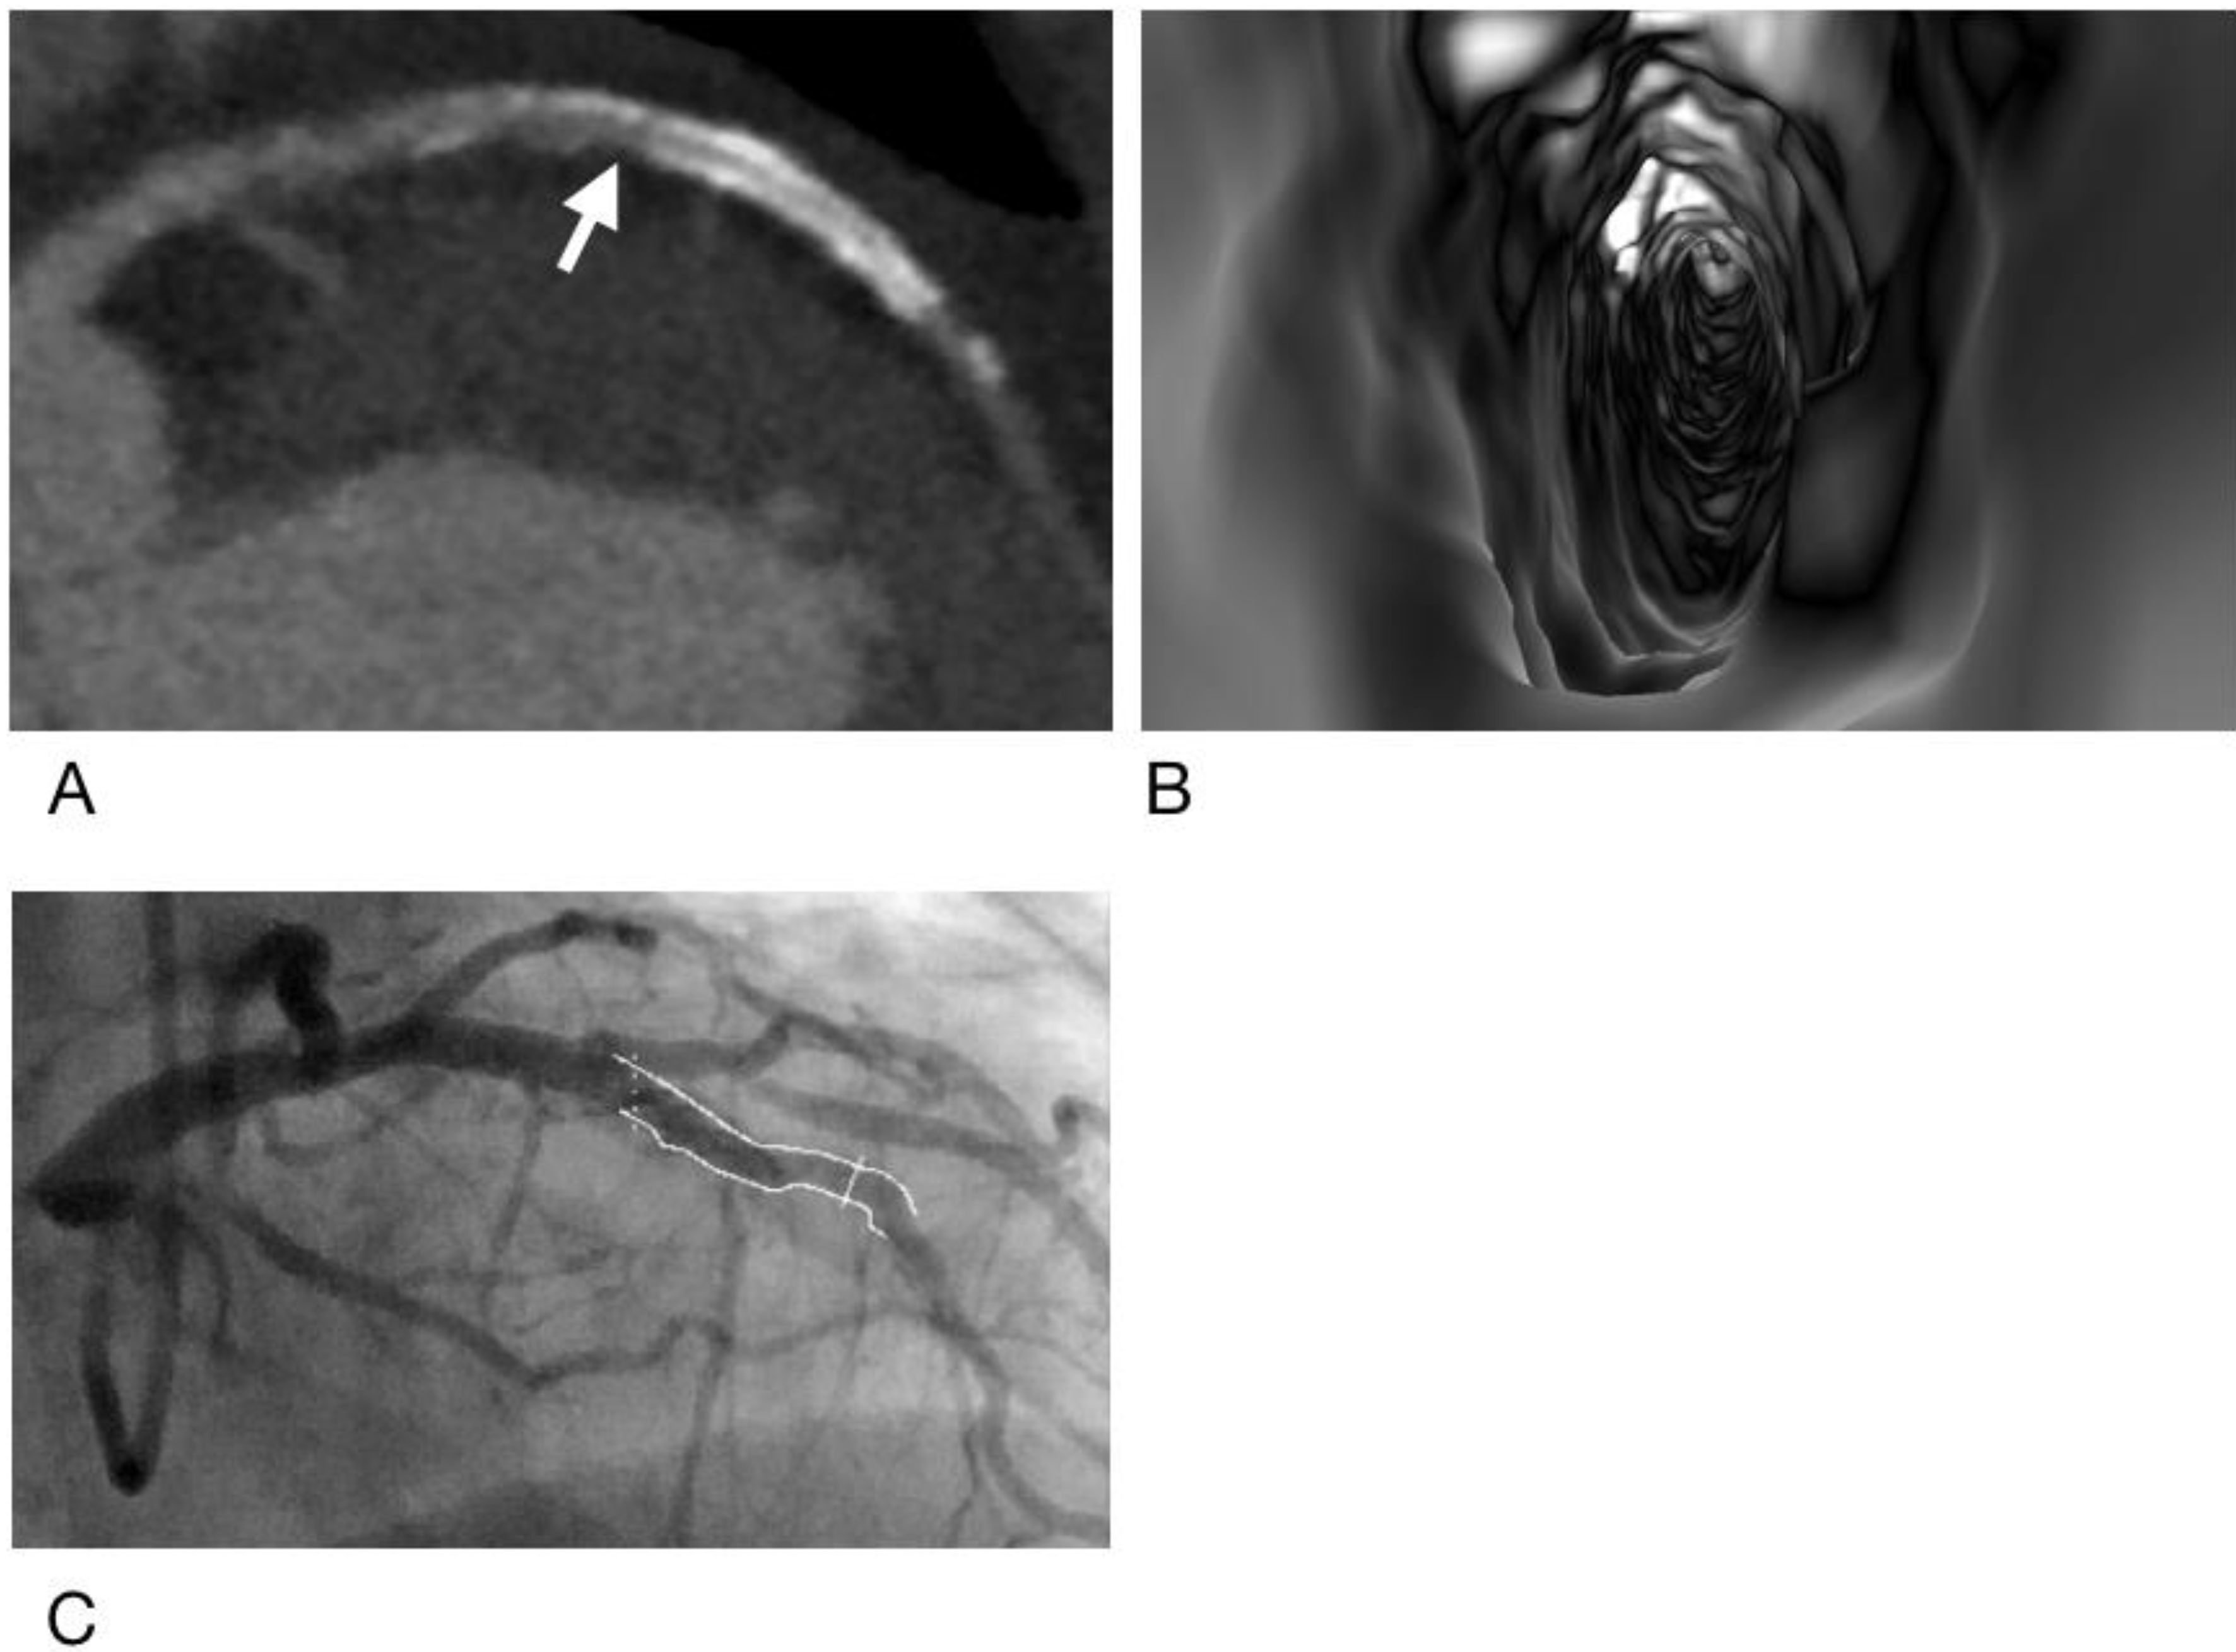

- Sun, Z.; Dimpudus, F.J.; Nugroho, J.; Adipranoto, J.D. CT virtual intravascular endoscopy assessment of coronary artery plaques: A preliminary study. Eur. J. Radiol. 2010, 75, e112–e119. [Google Scholar] [CrossRef] [PubMed]

- Xu, L.; Sun, Z. Virtual intravascular endoscopy visualization of calcified coronary plaques: A novel approach of identifying plaque features for more accurate assessment of coronary lumen stenosis. Medicine 2015, 94, e805. [Google Scholar] [CrossRef] [PubMed]

- Sun, Z.; Xu, L. CT virtual intravascular endoscopy in the visualization of coronary plaques: A pictorial essay. Curr. Med. Imaging Rev. 2017, 13, 154–161. [Google Scholar] [CrossRef][Green Version]

- Sun, Z. Coronary CT angiography in coronary artery disease: Correlation between virtual intravascular endoscopic appearances and left bifurcation angulation and coronary plaques. Biomed. Res. Int. 2013, 2013, 732059. [Google Scholar] [CrossRef]